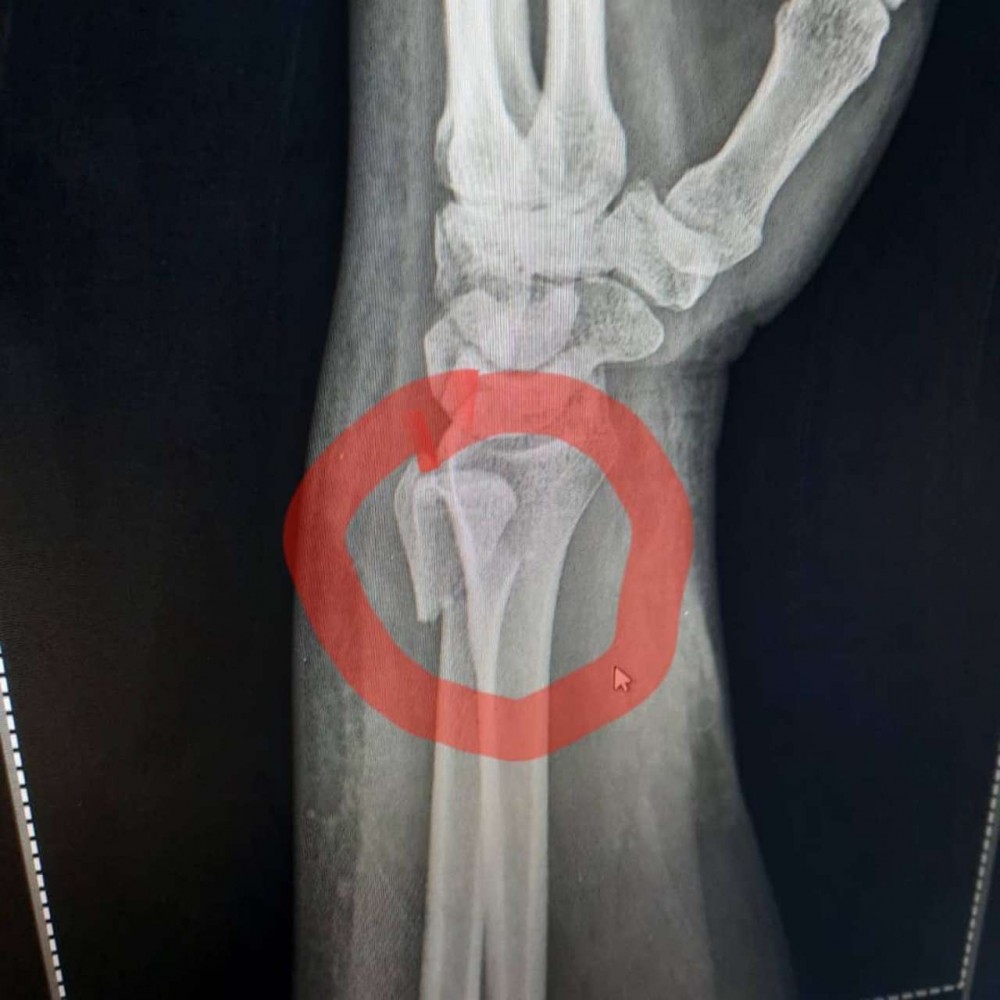

Azərbaycanlı aparıcının biləyi qırıldı - FOTOLAR

Tanınmış aparıcı Aytən Səfərovanın başına iş gəlib.

32gun.az xəbər verir ki, aparıcının bilək sümüyü sınıb. Bu barədə Səfərova instaqramda məlumat yayıb. O bildirib ki, bu günlərdə anası ağır əməliyyata hazırlaşır:

“Çox çalışdım ki, könlümü fərəh tutum, fikirləşdiyimi büruzə verməyim, özümü “sındırmayım”, lakin sümüyümü sındırdım. Həkimlər vaxtında müdaxilə etdilər. Hələ ki, ağrıkəsicisiz mümkün deyil, amma biz güclü qadınıq. İnşallah bu da keçər. Özünüzü qoruyun”.